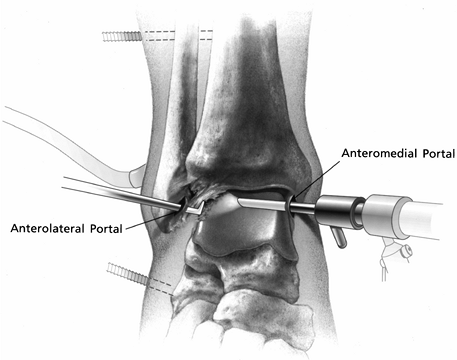

Insert a 90° microfracture awl for small lesions (Fig. 93.14A).![]() Figure 93.14. (See COLOR FIG. 93.14B, COLOR FIG. 93.14C and COLOR FIG. 93.14D). Arthroscopic treatment of osteochondral lesions of the talus. A: Figure 93.14. (See COLOR FIG. 93.14B, COLOR FIG. 93.14C and COLOR FIG. 93.14D). Arthroscopic treatment of osteochondral lesions of the talus. A:

The left ankle is shown. Viewing from the posterolateral portal, a

subchondral bone of a posteromedial lesion. B: Microfracture of the subchondral surface using an awl. C: Using a drill guide for transmalleolar drilling of the subchondral bone. D: The result of the above two treatments is a bleeding bone surface providing vascular access for cartilage formation.

For larger lesions, use a 90°

microfracture awl along the peripheral edge of the lesion and use a

MicroVector (Smith and Nephew, Endoscopy, Andover, MA) to drill

multiple holes in the center of the lesion (Fig. 93.14B and Fig. 93.14C; see COLOR FIG. 93.14B, COLOR FIG. 93.14C and COLOR FIG. 93.14D).